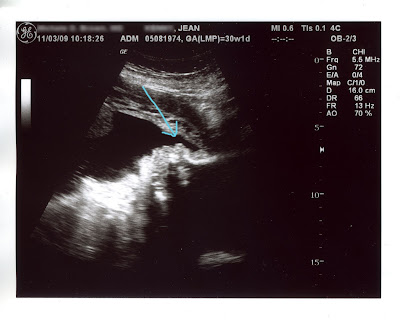

Here's her chin:

Do you see that? It's her left profile. Got that?

Now I understand that you probably have never seen my grandmother, and maybe this isn't the most accurate photo of leftie since it's just an ultrasound, so maybe I'll change my mind about it when she's on the outside, but from my viewpoint, that's my grandma's chin. You'll just have to take my word for it.